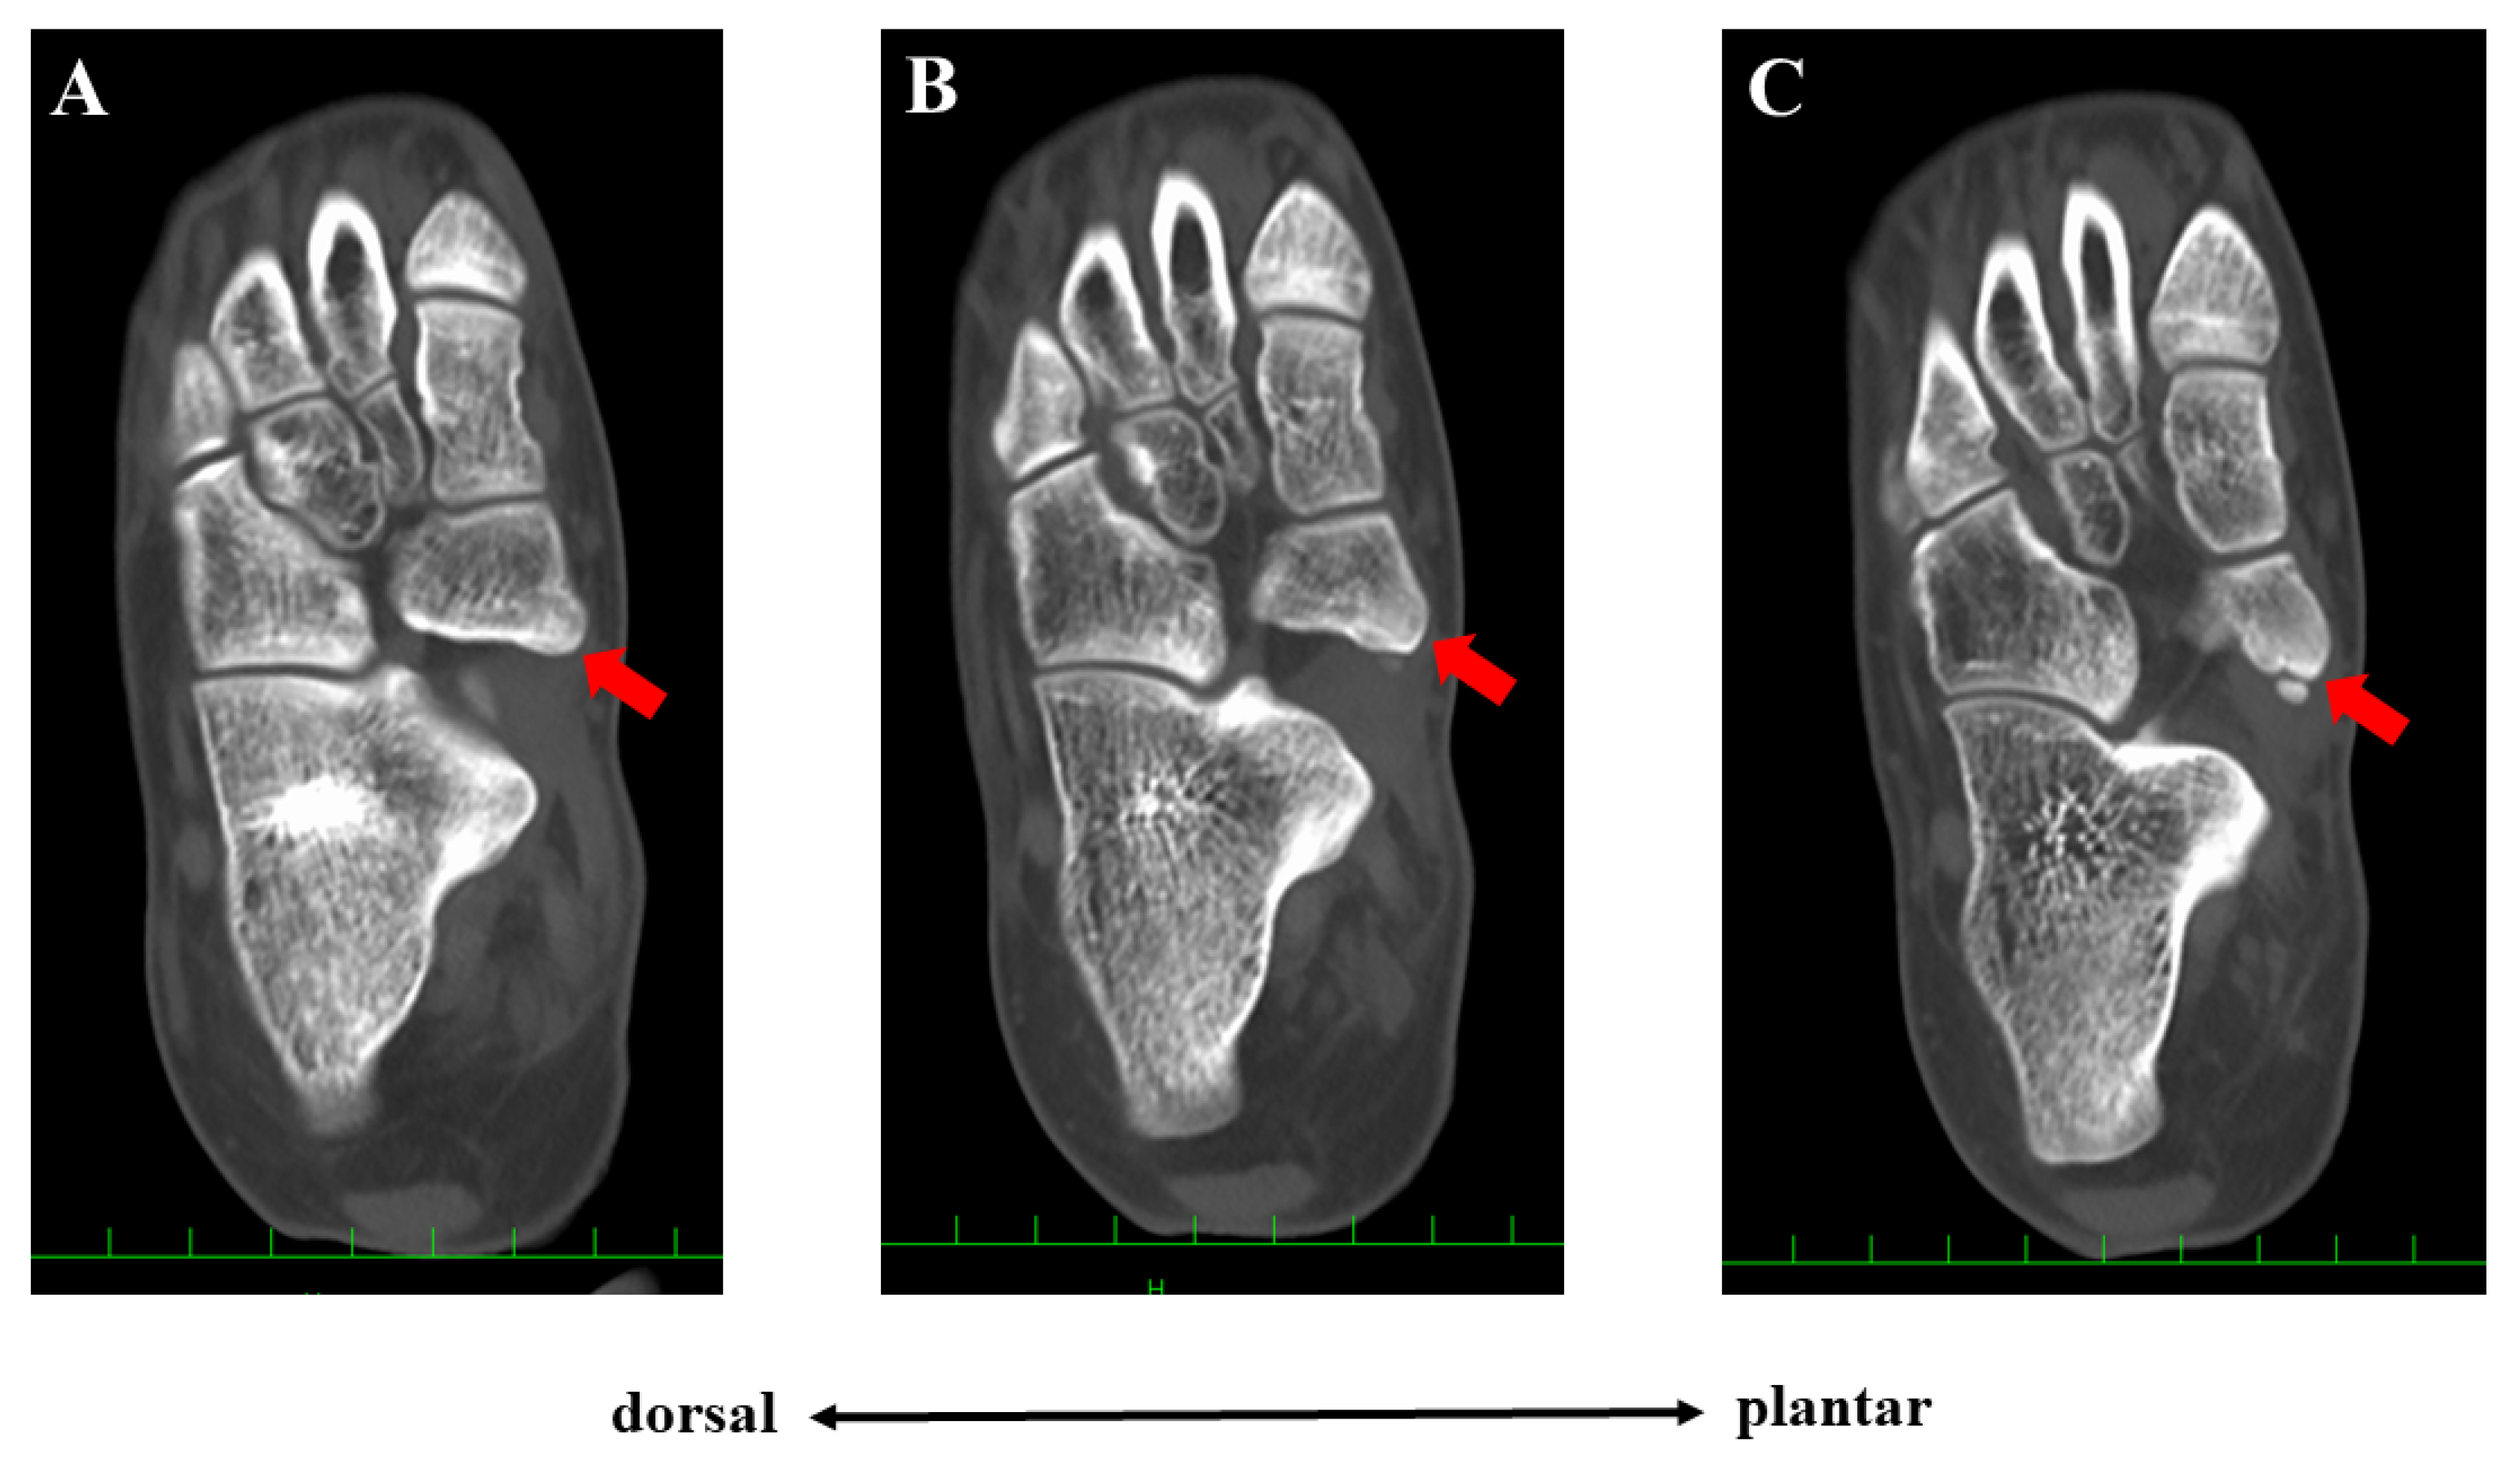

Conservative treatment including physiotherapy, medication for pain, and the application of an insole had been performed for more than one year but failed to completely remove her symptoms. She had been active in soccer, and her training experience was three years at the time of first presentation. She had tenderness at the navicular tuberosity with the exacerbation of pain while weight bearing. Plain radiographs did not show specific findings of flatfoot (Meary’s angle, 19.8 degrees; calcaneal pitch angle, 4.6 degrees) or hindfoot malalignment. Computed tomography (CT) showed a small AN and prominent navicular tuberosity with a high Hounsfield unit (HU) value (Figure 2). A low signal lesion was identified in the prominent part of the navicular bone on the T1-weighted image of the magnetic resonance imaging (Figure 3).

Figure 2.

Preoperative computed tomographic findings. Three continuous axial scans at the lesion level are shown (A–C). The united ossicle of the accessory navicular (red arrow) showed a higher Hounsfield unit than the adjacent normal cancellous bone.

The Veitch classification is the system most commonly used to evaluate patients with AN [5,6,7,8]. This classification is easy to understand and broadly used in clinical practice. However, various kinds of morphologies of the AN have been reported [2,10]. Furthermore, Perdikakis et al. first reported a case of multiple ANs [11]. Kalbouneh et al. reported that multiple ossicles were radiographically detected in 1.2% of cases with ANs [10]. The authors also reported that the larger ossicle was united to the navicular while the other round ossicle was clearly separated from the navicular bone, which was similar to the present case. In the present case, the patient had been treated conservatively for Veitch type 1 AN probably because few studies have reported the surgical management of type 1 AN [7]. However, tenderness was present at the united ossicle (navicular tuberosity), not at the separated small ossicle, indicating that the cause of foot pain was derived from the united ossicle. The lesion with high HU on CT images also suggested continued stress loading on the united ossicle. Therefore, from the viewpoint of the pathology, the present case could be classified as Veitch type 3 AN. Clinicians should not simply classify patients with AN into three types using the Veitch classification because this may lead to inappropriate management as presented in the present case.